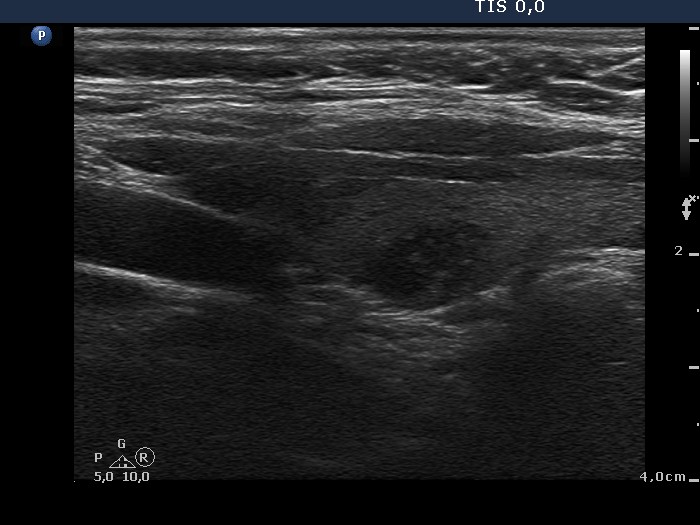

Chronic lymphocytic thyroiditis - Case 45. |

Clinical presentation: a 54-year-old patient was referred for an evaluation of a 'nodular goiter' detected on a sonographic screening.

Functional state: subclinical hypothyroidism (TSH 5.18 mIU/L, FT4 12.4 pM/L).

Ultrasonography: the thyroids contained multiple hypoechogenic areas. These do not fit a nodule because of their shape. See longitudinal sections and video.

Comment: it is worth to analyze the video and the longitudinal section of the left lobe. In contrast with a true nodule, these hypoechogenic areas are irregular in shape.